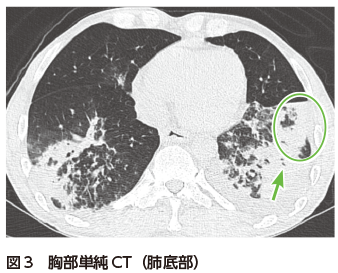

胸部単純X線写真では両下肺野に浸潤影を認める(図1).胸部CTでは両肺下葉の末梢気管支周囲に浸潤影およびすりガラス影の散在を認める(図2).肺底部は胸膜側優位に気管支透亮像を伴う広範な浸潤影を認める(図3).一部は非区域性に分布している(図3).

器質化肺炎の陰影は,気管支血管束周囲や胸膜下に分布することが多く,斑状影や浸潤影を呈する.浸潤影は内部に気管支透亮像を伴う.しばしばその分布は非区域性(気管支の支配領域を横断する形の分布)である2)